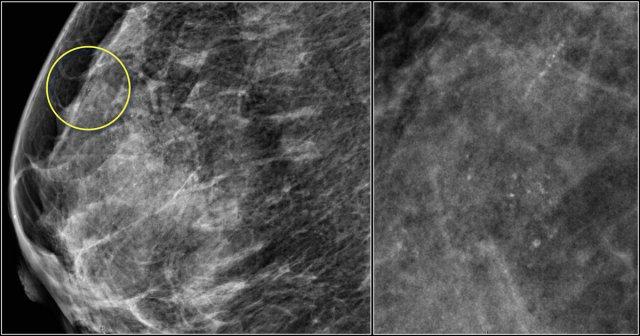

Lưu ý ở ví dụ bên trái, thành phần tuyến vú được phân loại là c – mật độ không đồng nhất, mặc dù thể tích mô tuyến xơ chiếm dưới 50%.

Mô tuyến xơ ở phần trên có mật độ đủ cao để che khuất các khối nhỏ.

Do đó được phân loại là c, vì các khối nhỏ có thể bị che khuất.

Theo phân loại cũ, trường hợp này sẽ được gọi là ACR 2: mật độ 25-50%.

Ví dụ bên phải có hơn 50% mô tuyến và cũng được phân loại là thành phần c.